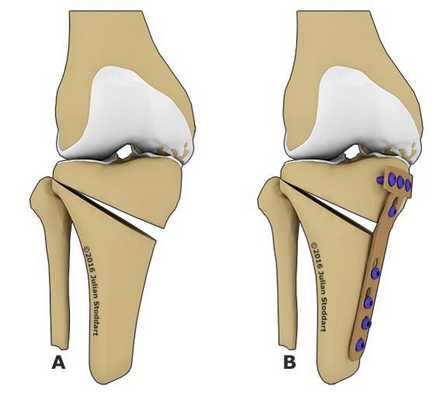

Корригирующая остеотомия коленного сустава

Что такое корригирующая остеотомия коленного сустава?

Это оперативное вмешательство, при котором, путем хирургической манипуляции на большеберцовой или бедренной кости, достигается эффект смещения круговой оси распределения нагрузки на нижнюю конечность и придания ей более физиологического положения.

Как проходит операция

Смысл проводимого оперативного вмешательства заключается в том, что на кости со стороны наибольшего поражения сустава делается надрез, отверстие необходимой формы. После этого в это отверстие помещается необходимое количество собственного костного или хрящевого вещества, благодаря чему конечность как бы отводится в сторону, отклоняется по оси тела в противоположном от патологического процесса направлении.

Остеотомия с металлоконструкцией

Далее, участок кости, на котором произведен надрез с помещенным туда костным аутоимплантом, фиксируется титановой пластиной при помощи винтов. Затем доступ ушивается, а конечность иммобилизируется при помощи шины или лангеты. В наложении гипса необходимости нет.